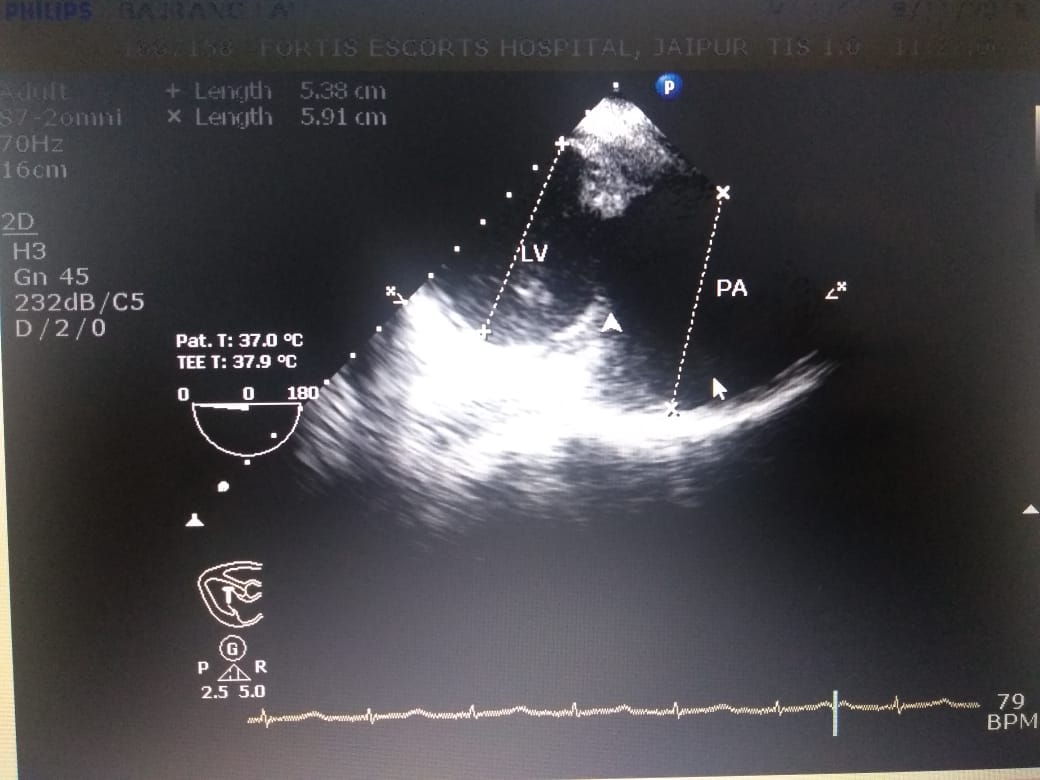

aortic bifurcation. On further investigation he was found to have CONTAINED RUPTURE OF LEFT

VENTRICLE WITH LARGE COMMUNICATING PSEUDOANEURYSM WITH CLOTS.

An emergency bilateral femoral embolectomy as first stage followed by a successful patch closure of

LV wall rupture was done (a procedure which carries upto 50% mortality world over)